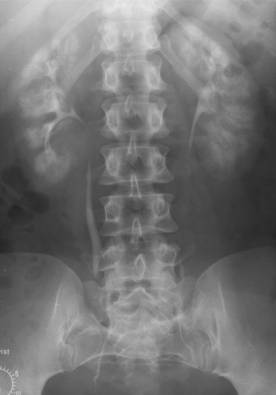

Fig. 57 – Staza prepapilara bilaterala

e) staza - renala - poate fi determinata de obstacole organice sau functionale pe calea de excretie. Se manifesta radiologic prin cresterea intensitatii umbrei renale. in staza totala se opacifica numai parenchimul = nefrografie electiva (fara pielografie). in staza partiala se opacifica si calicele, bazinetul si ureterul= nefrografie cu pielografie; - pe caile urinare - se datoreaza unui obstacol incomplet, aparand imagini de intensitate crescuta, nete = 'imagini foarte frumoase' (Colliez). In functie de gradul obstructiei si localizare deosebim: staza prepapilara, caliceala, pielocaliceala si ureterala.